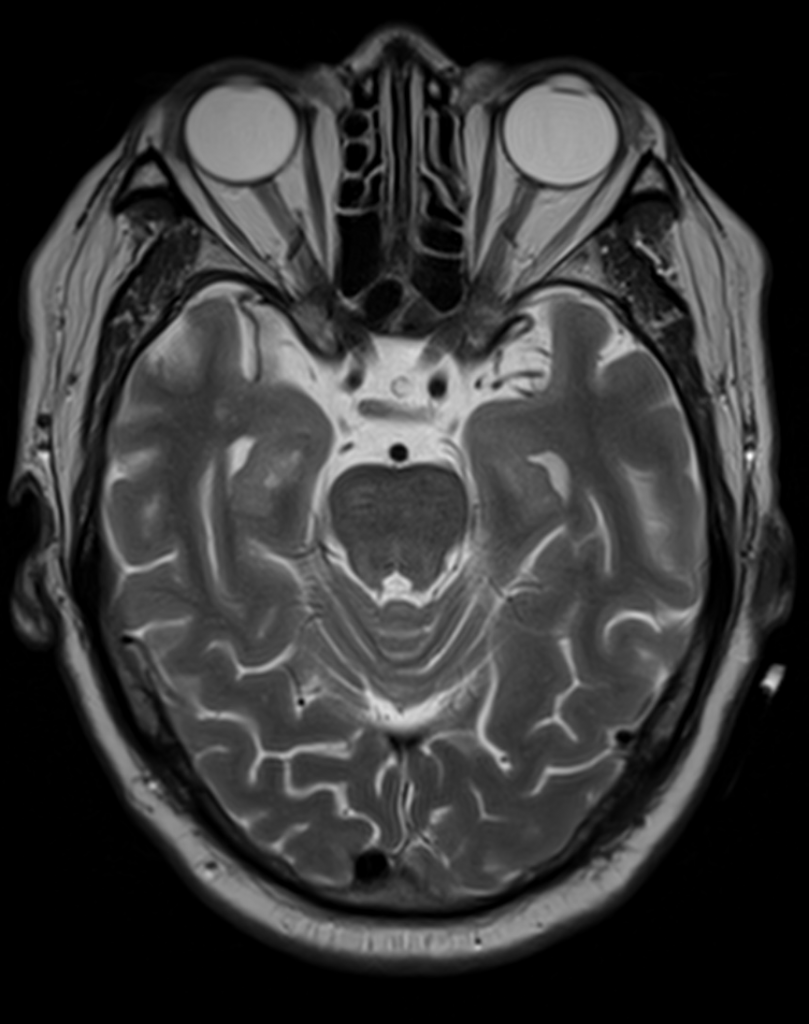

Clinical Images